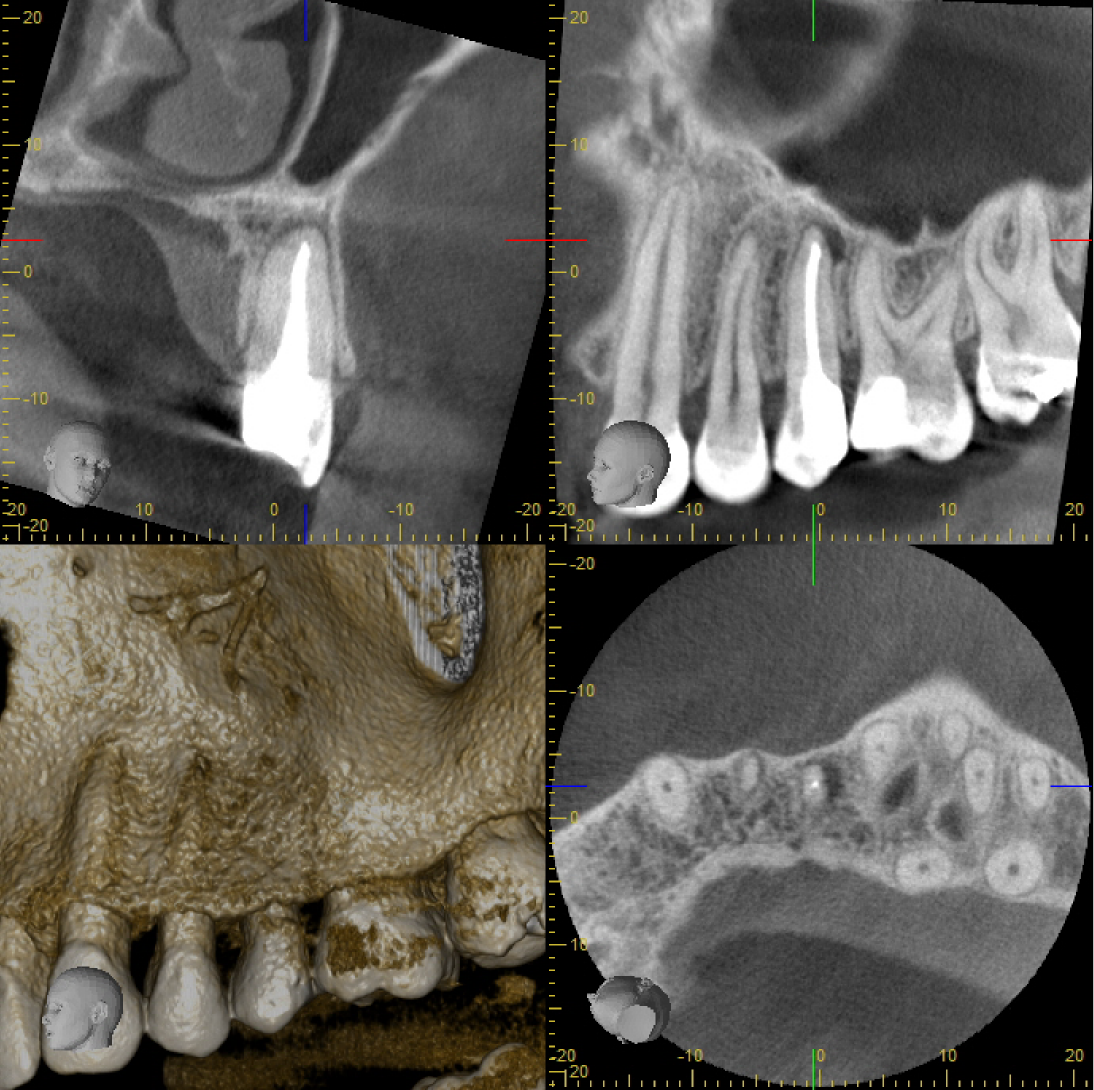

Bildschirmfoto DVT 25 Veröffentlicht 13. Oktober 2014 am 1094 × 1090 in Fragestellung: Parodontitis apicalis? (2)